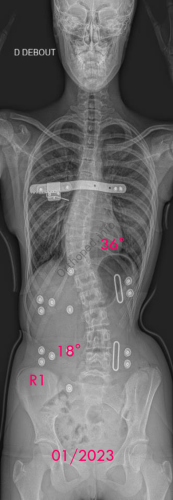

Images de scolioses opérées 16 janvier 202418 janvier 2023 par Damien Scoliose idiopathique - VBT -1 Chirurgie de modulation de croissance (VBT) Scoliose idiopathique - VBT -1 - pré-op Scoliose idiopathique - VBT -1 - pré-op en traction Cliché réalisé pour tester la réductibilité de la scoliose Scoliose idiopathique - VBT -1 - post-op immédiat Scoliose idiopathique - VBT -1 - 3 mois post-op Scoliose idiopathique - VBT -1 - 10 mois post-op